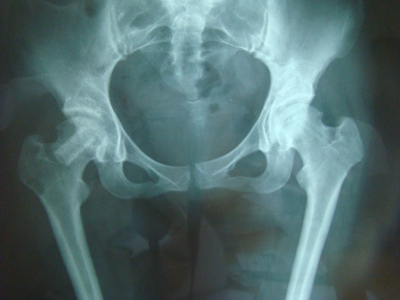

5.支撑架植入术近一个世纪以来,临床医生采用髓内减压加植骨、血管植入、带肌瓣或带血管骨瓣移植等方法试图重建股骨头的血运,但均因股骨头内缺乏有力的支撑而无法阻止股骨头的进一步塌陷。杨述华等[13,14]为防止股骨头塌陷,为坏死股骨头软骨下骨板提供足够的力学支撑,设计了呈圆柱状中空带螺纹同种异体骨支撑架,通过髓芯减压隧道植入到坏死区软骨下骨板下,防止股骨头塌陷,同时将自体松质骨和DBM放入支撑架内,治疗早期股骨头坏死,取得满意效果,为股骨头的治疗提供了一种崭新的思路(图3)

(图3)圆柱状中空带螺纹同种异体骨支撑架植入